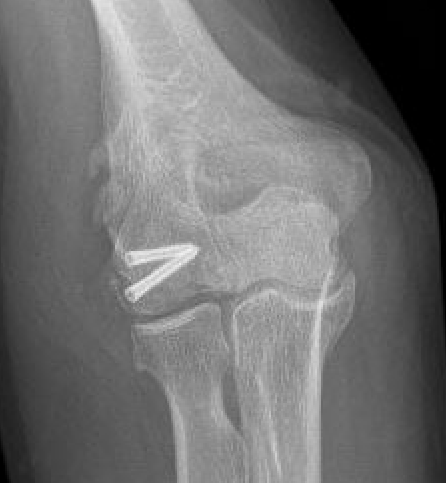

Capitellum fracture with radial head dislocation due to LCL injury

LCL

Dubberley et al JBJS Am 2006

- 27 capitellum fractures treated with surgery

- 41% had associated LCL injuries

- 7/11 LCL injuries were avulsion fractures of the lateral epicondyle